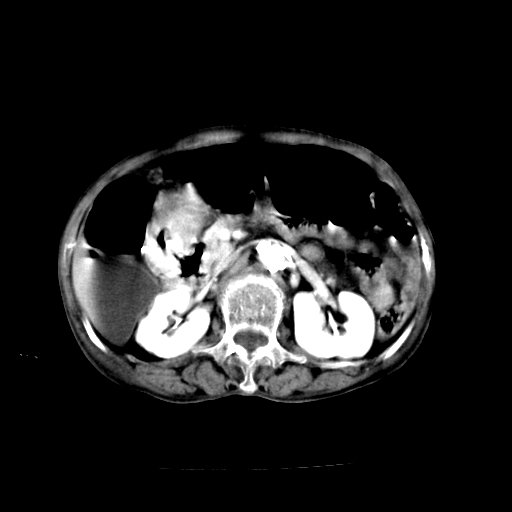

标题: CT19149:女,68岁,腹胀、恶心两周。 [打印本页]

女,68岁,腹胀、恶心两周,先做ct平扫,当时家属不同意强化,6天后家属要求增强扫描。

1)胃窦壁厚,考虑胃窦癌?建议行胃镜检查。 2)局灶性脂肪肝。